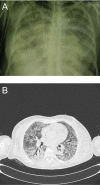

Lobar fiberoptic lung lavage is a well-known procedure used in primary pulmonary alveolar proteinosis (PAP); the use of this procedure has increased in the recent years. This procedure has also been used in other pulmonary diseases such as desquamative interstitial pneumonia with good results. We describe a case of extremely severe respiratory failure due to concurrence of PAP and Influenza A H1N1 virus pneumonia which resolved with the help of this procedure. The patient, a 41-year-old woman, needed less mechanical ventilation after undergoing lobar fiberoptic bronchoscopic lavage. Moreover, a rapid and progressive improvement in the computed tomography of the lungs was observed. Flexibile fiberoptic bronchoscopic lobar lavage is a simple, safe procedure used not only in milder disease, but also in particular severe cases in which the physiological derangement of whole lung lavage would not be tolerated by patient or when extra-corporeal membrane oxygenation is not available.